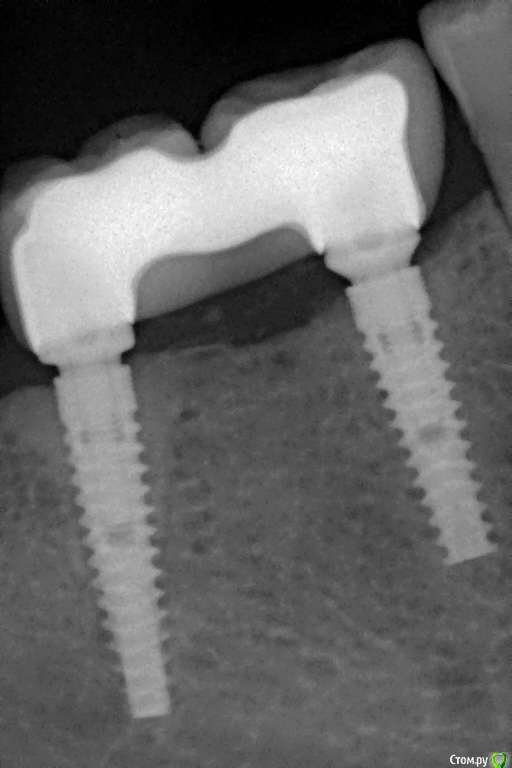

Pavel-Pskov Опубликовано 24 мая, 2016 Поделиться Опубликовано 24 мая, 2016 В момент снятия слепков май 2014 г.Неделя назад Ссылка на комментарий